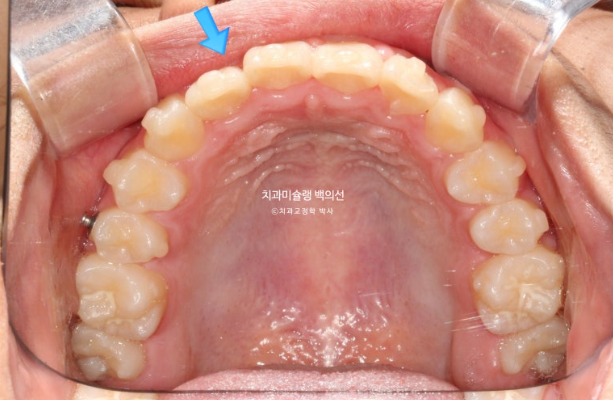

254년 10월부터 25년 1월까지 14개 추가장치를 모두 낀 후 모습입니다.

25.01

추가장치에서 중심선 개선을 위한 고무줄을 처방했는데 아이가 고무줄을 너무 열심히 껴준 덕에 중심선이 오히려 3개월 전에 비해 반대로 넘어간 것이 보입니다.

이런 경우 고무줄을 중단하면 어느정도 원래 위치로 돌아오기 때문에 마지막 꼈던 14단계 장치를 유지용으로 잘때만 끼면서 경과 관찰을 하기로 합니다.

그렇게 4개월간 경과관찰을 하던 중 25년 5월 내원시 모습입니다.

25.05

예상대로 고무줄을 중단하자 중심선이 재발이 어느정도 일어나 좋아졌으나

잘때만 끼도록 했던 마지막 장치를 잘 안 꼈는 지 앞니 배열이 다시 틀어졌습니다.

이 부분을 바로잡기 위해 부득이하게 2번째 재제작에 들어갑니다.

교합과 아래배열은 완벽하게 유지되고 있습니다